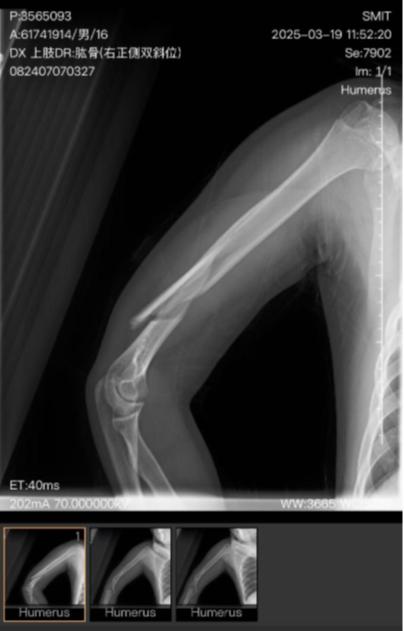

小明右肱骨医学影像

秦皇岛市第一医院一份手术记录显示,3月21日,小明因右肱骨粉碎性骨折、右桡神经损伤进行手术治疗。